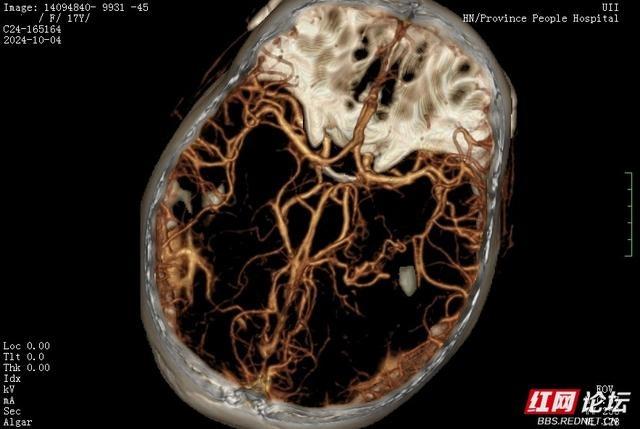

小雯抵达医院后,急诊科对她进行了头部CT扫描。结果显示,她的颅内发生了出血。不久,她被转移至神经外科一病区。经过头部CTA和DSA检查,诊断结果为“右侧颞顶枕叶脑出血破入脑室”,同时伴有“大脑血管动静脉畸形”。病情相当严重,神经外科的医生们对此高度重视,不敢有丝毫懈怠。

手术过程中,外科团队面临了严峻挑战。他们必须在清除血肿及切除血管畸形的过程中,小心避免损伤邻近的肢体运动功能区神经纤维。头部CT及CTA检查显示,血管畸形团与神经纤维紧密相邻。孙圣礼主任在手术中犹如在细如钢丝的生命线上行走,每一步都需极为谨慎,以避免对小雯造成不可逆转的伤害。

孙圣礼主任医师带领的团队与麻醉科手术室团队通力合作,手术过程顺利进行。术后,小雯转入恢复阶段,神经外科一病区的医护团队精心护理,她的健康状况逐渐好转。复查CTA检查发现,血管畸形已完全消失,这一好消息让所有关注小雯的人们感到安心。